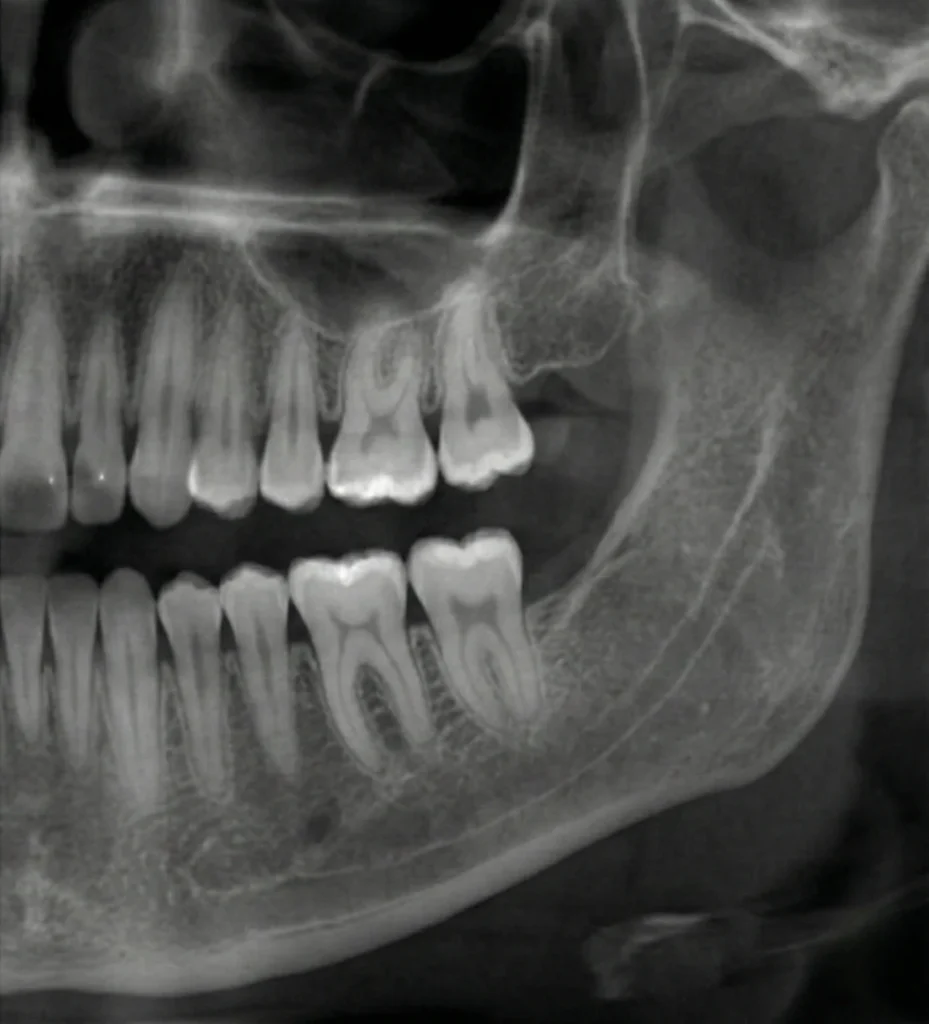

Not every wisdom tooth requires the same type of extraction. Fully erupted wisdom teeth may be removed with a simple extraction using local anesthesia. Teeth that are impacted beneath the gums or bone often require a surgical approach to allow safe removal.

Sedation options such as nitrous oxide, oral sedation, or IV sedation may be used based on comfort needs, with care provided through sedation dentistry when appropriate. Treatment decisions are guided by X-rays, age, oral health, and individual comfort considerations.